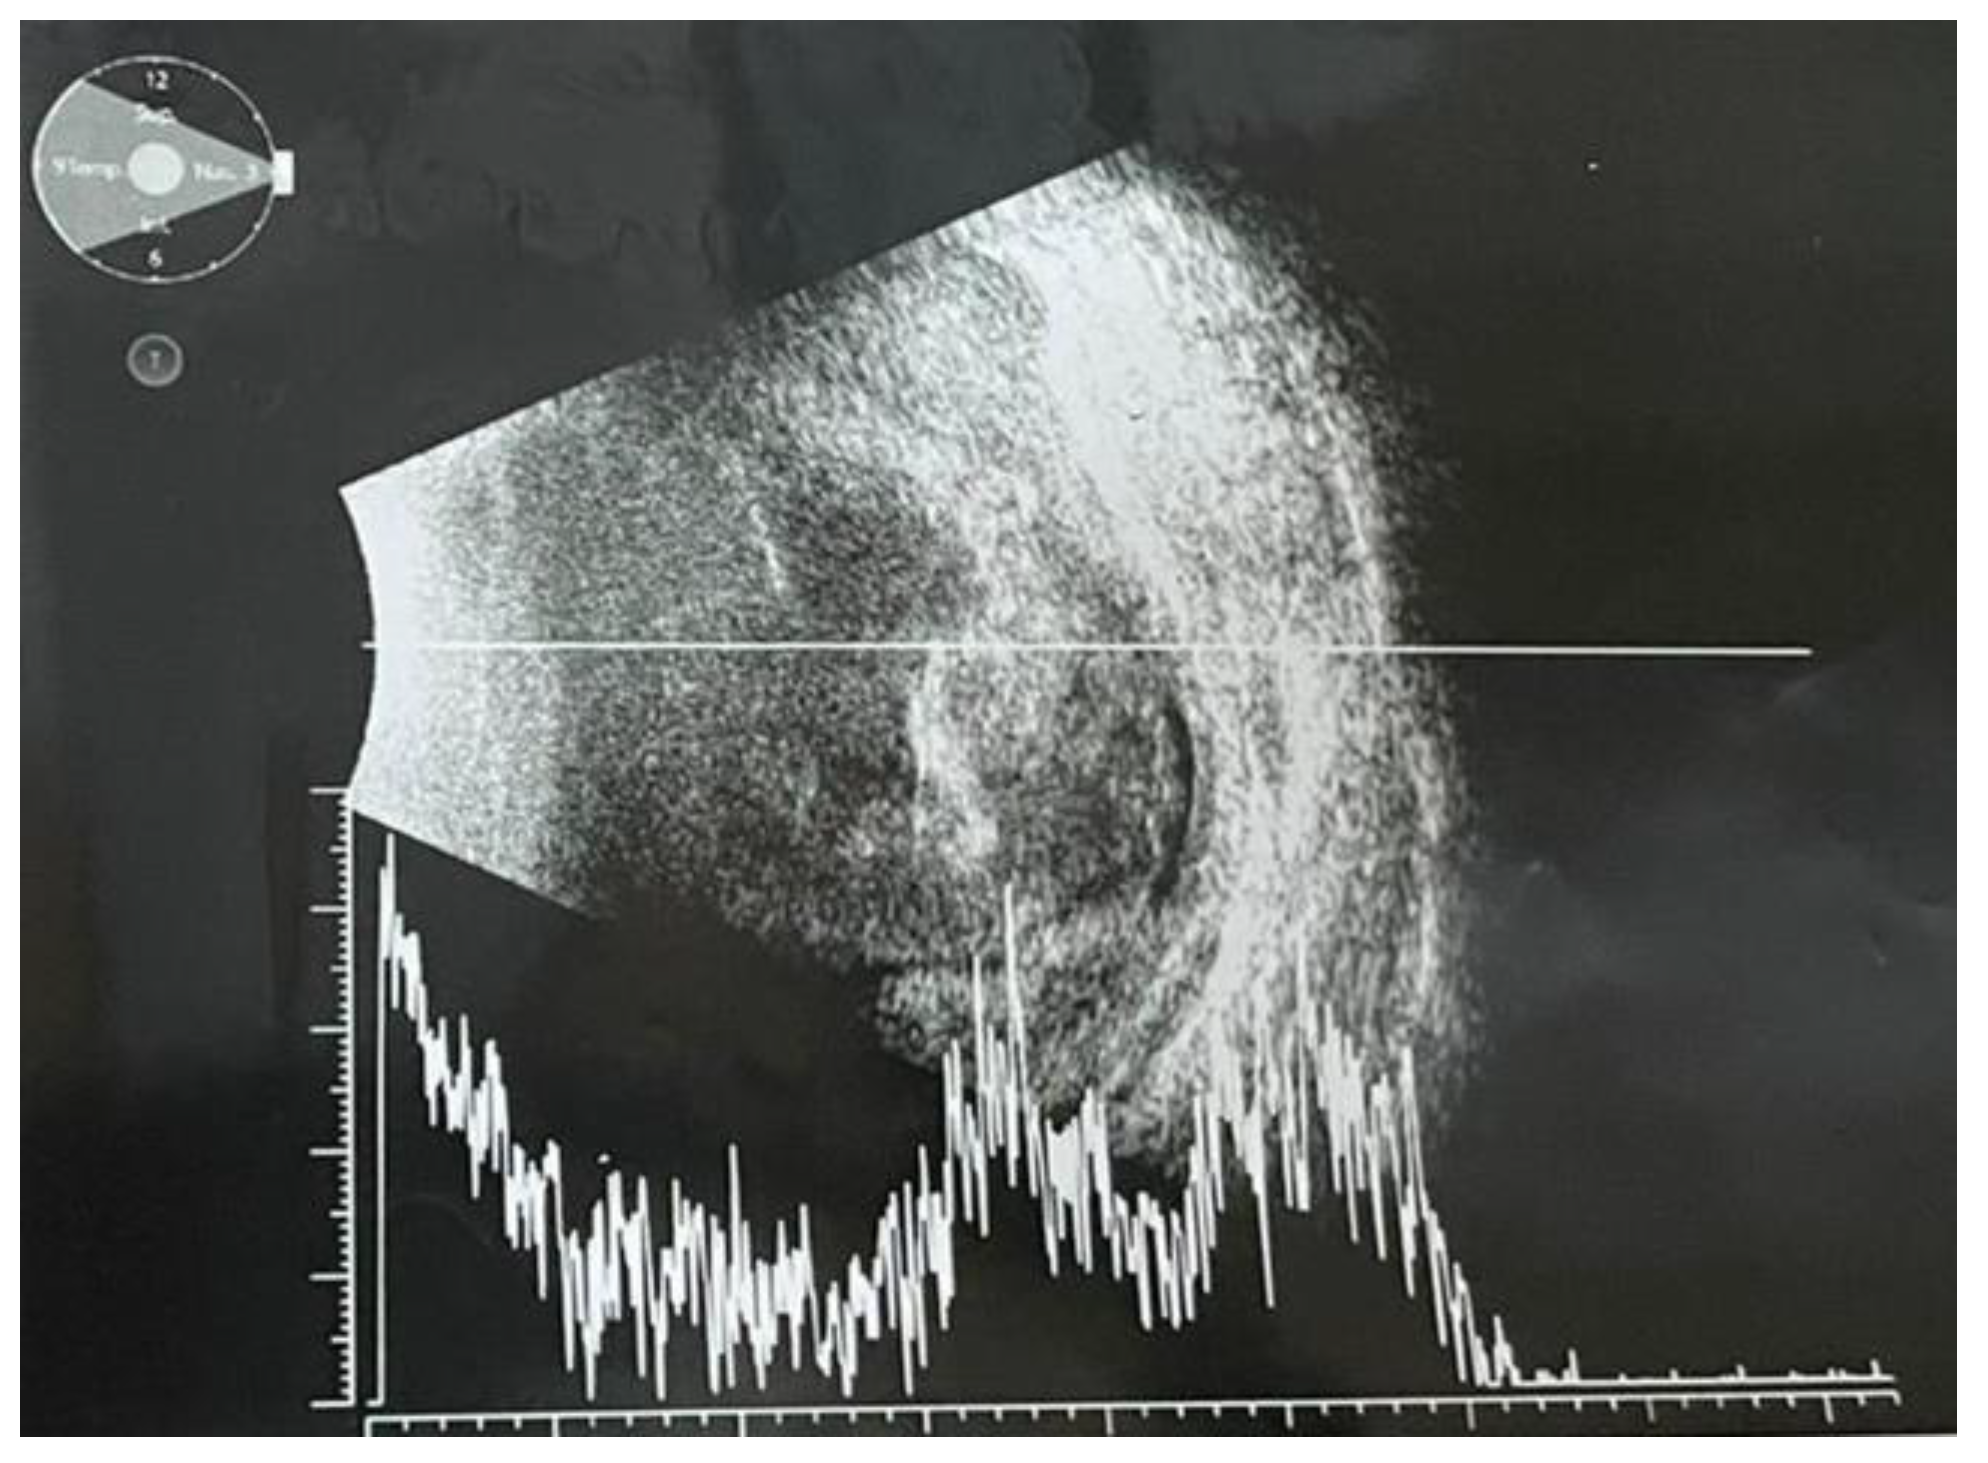

Ultrabiomicroscopy (UBM) confirmed posterior irido- lenticular synechiae on 360⁰ and thickening of the ciliary body (Figure 1). Ocular ultrasound exam revealed total retinal detachment, multiple fine vitreous echoes suggestive for vitritis, homogeneous thickening of the choroid and a 3mm diameter hyperechogenic mass invading sclera (Figure 2). A differential diagnosis between an extrascleral extension of an endophthalmitis and a possible intraocular tumor with scleral penetration was considered.

Figure 1.

Ultrabiomicroscopy: circumferentially posterior synechiae and ciliary body thickening.